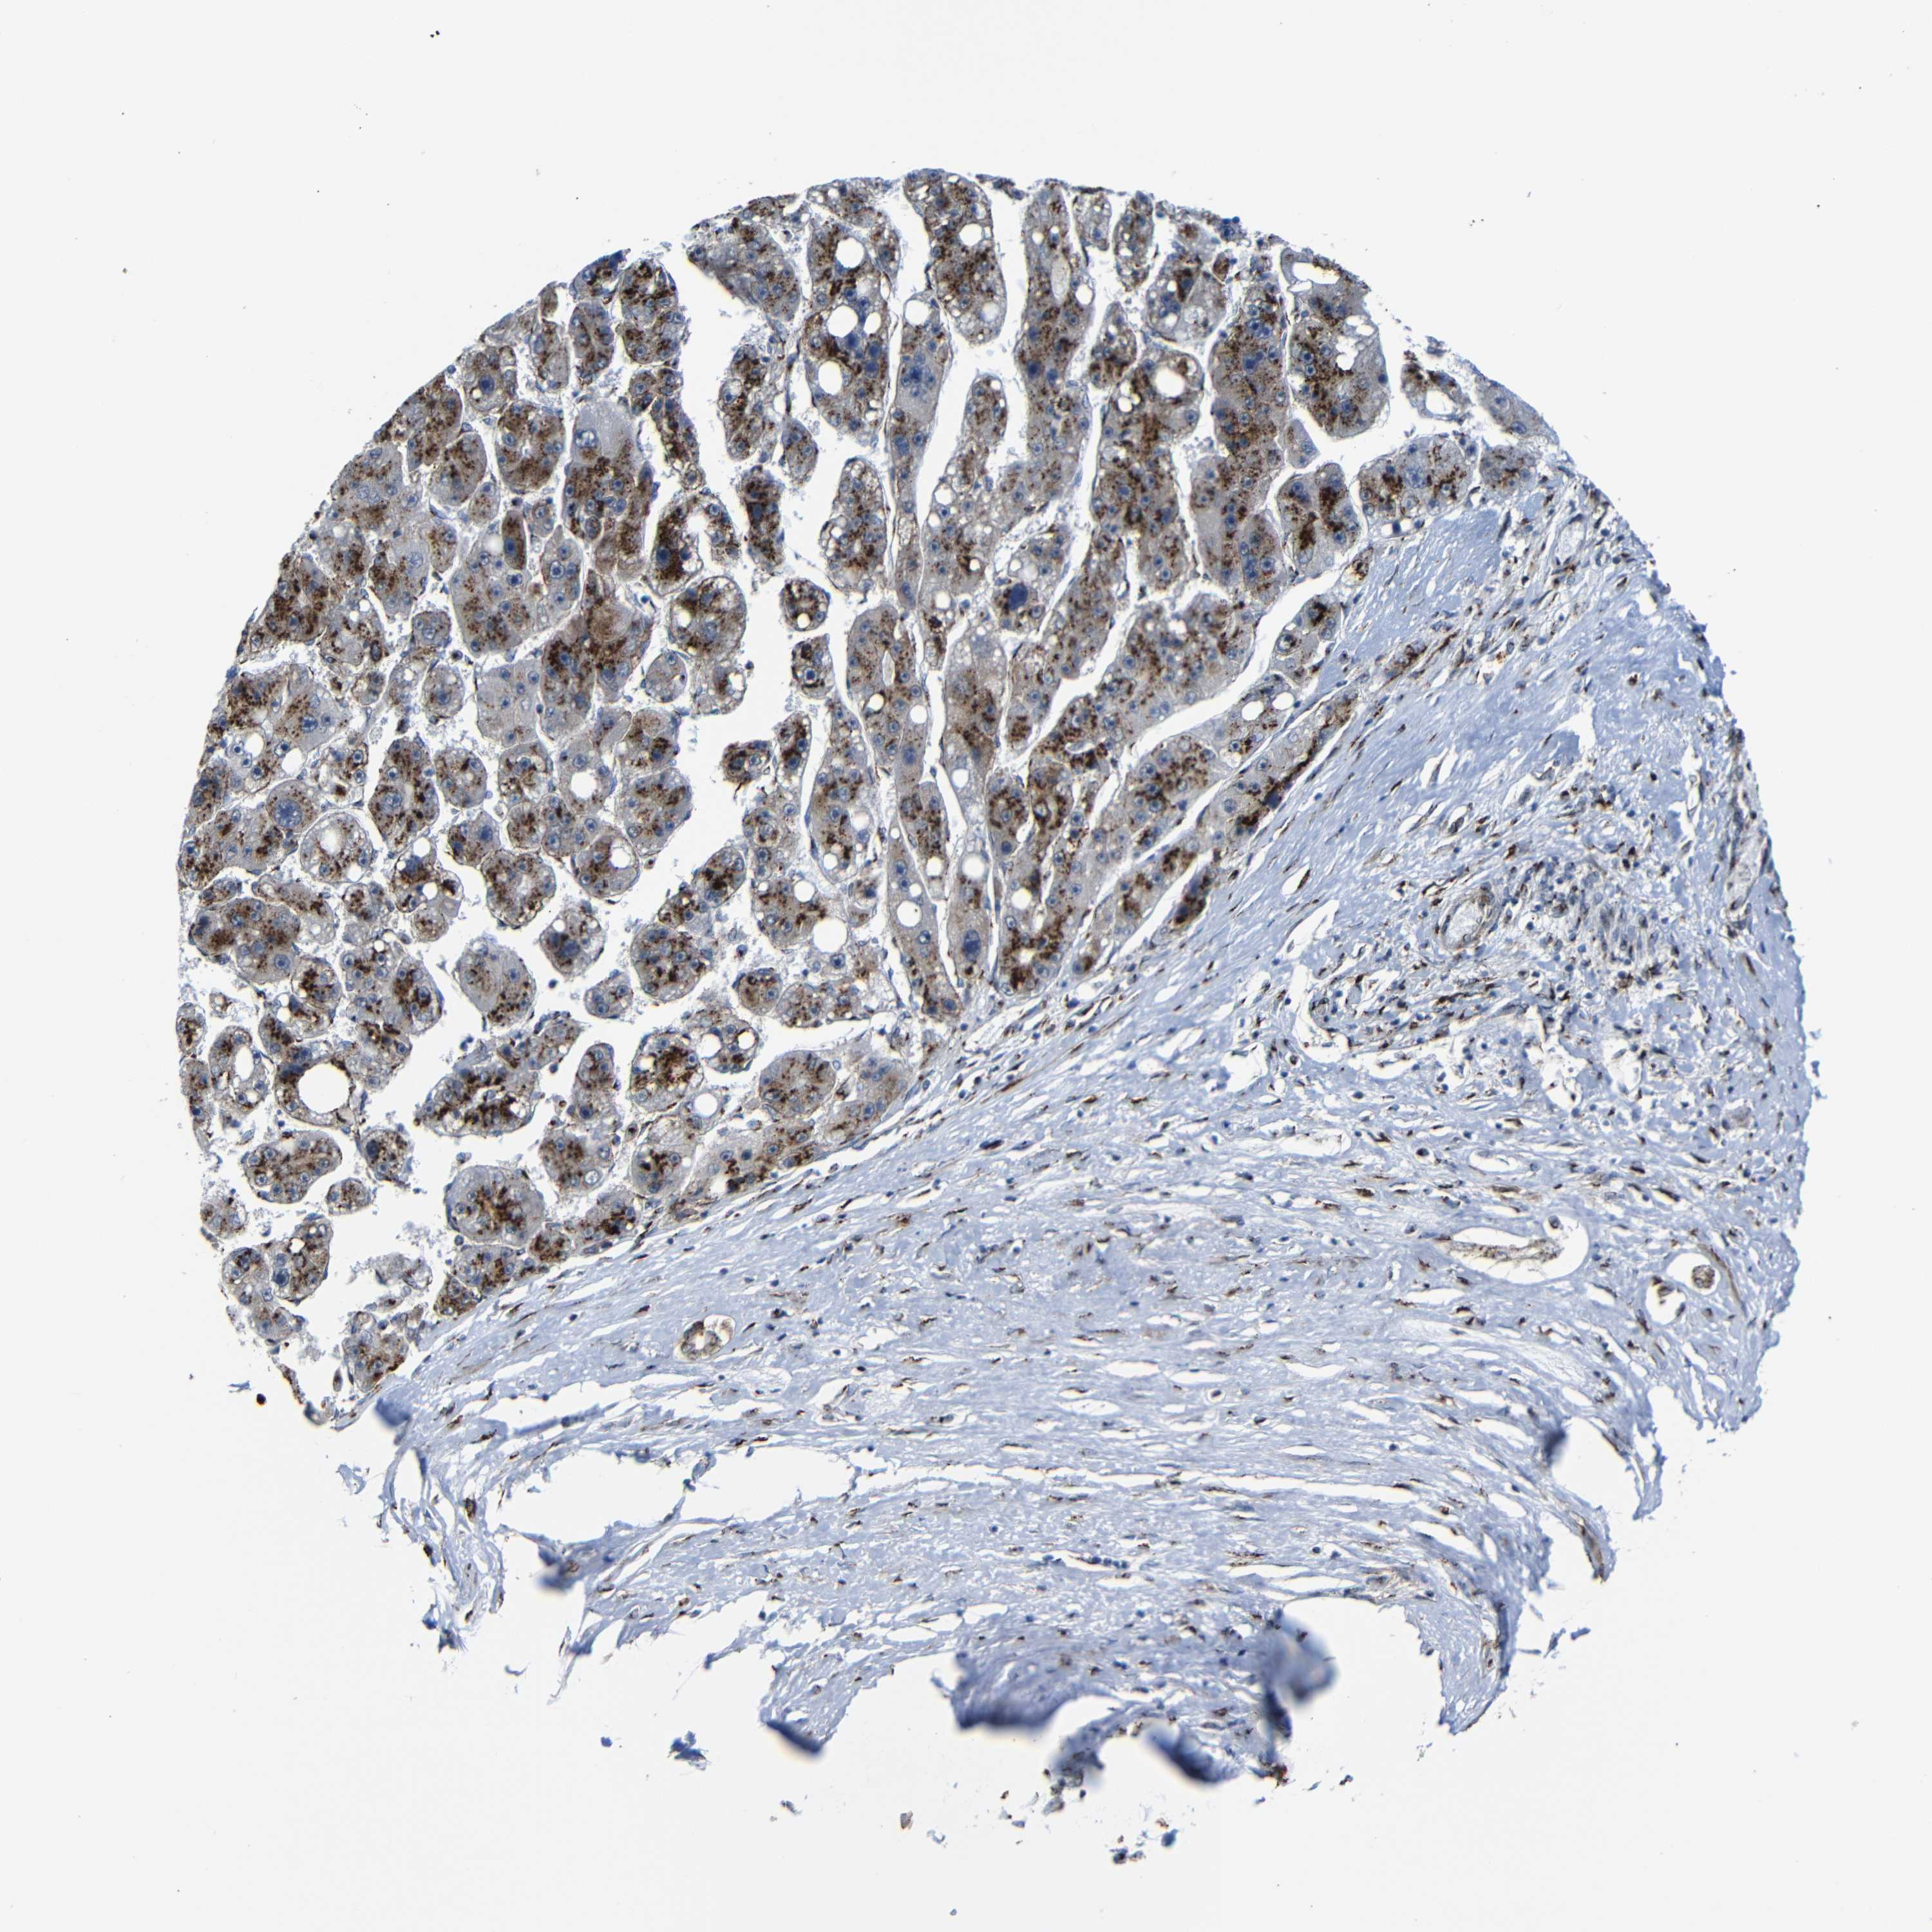

LIVER CANCER - Protein expressioni

A mouse-over function shows sample information and annotation data. Click on an image to view it in a full screen mode. Samples can be filtered based on level of antibody staining by selecting one or several of the following categories: high, medium, low and not detected. The assay and annotation is described here.

Note that samples used for immunohistochemistry by the Human Protein Atlas do not correspond to samples in the TCGA dataset.

Antibody stainingi

Antibody staining in the annotated cell types in the current human tissue is reported as not detected, low, medium, or high, based on conventional immunohistochemistry profiling in selected tissues. This score is based on the combination of the staining intensity and fraction of stained cells.

Each image is clickable and will lead to virtual microscopy that enables deeper exploration of all samples and also displays staining intensity scores, fraction scores and subcellular localization as well as patient and tissue information for each sample.

Antibody HPA012609

Antibody HPA012723

Antibody CAB011489

Staining

High

Medium

Low

Not detected

Intensity

Strong

Moderate

Weak

Negative

Quantity

>75%

75%-25%

<25%

None

Location

Nuclear

Cytoplasmic/membranous

Cytoplasmic/membranous,nuclear

Cholangiocarcinoma

Carcinoma, Hepatocellular, NOS